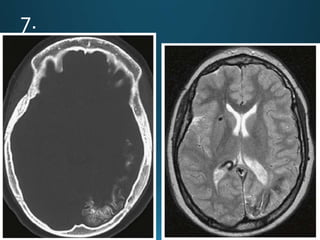

État criblé, also known as status cribrosum, is a term that describes the diffusely widened

perivascular spaces (Virchow-Robin spaces) in the basal ganglia, especially in the corpus

striatum. It is usually symmetrical, with the perivascular spaces showing CSF signal and

without diffusion restriction